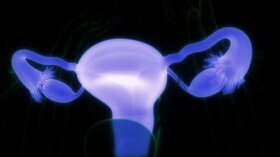

유피낭종은 모발, 치아, 체액 및 선 조직을 포함하는 주머니의 성장이다. 두개골, 척수, 얼굴 및 난소에서 형성될 수 있는 난소 유피낭종…